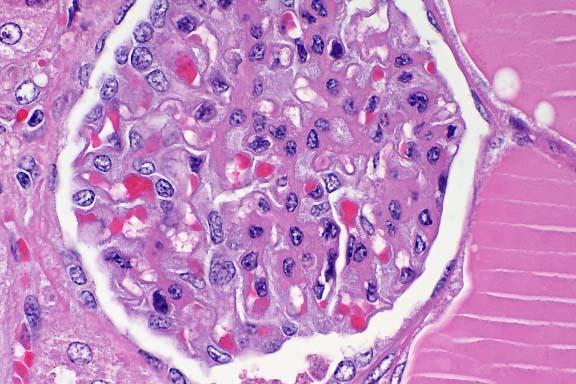

- Case 8-4. Kidney. Hematopoietic cells are largely

replaced by hemorrhage and congestion which expands the interstitium

and separates tubules.

- Case 8-4. Kidney. Multifocally, tubular epithelium

is necrotic.

- Case 8-4. Multifocally and randomly throughout the

hepatic parenchyma, there are pale zones of hepatocellular necrosis

(loss of cell detail, karyolysis, pyknosis, & cell loss).

- 1. Trunk kidney: Congestion and hemorrhage, diffuse, moderate,

Atlantic salmon (Salmo salar), piscine.

2. Liver, hepatocytes: Degeneration and necrosis, multifocal.

3. Kidney: Necrosis, tubular epithelium, multifocal.

4. Spleen: No significant lesions.